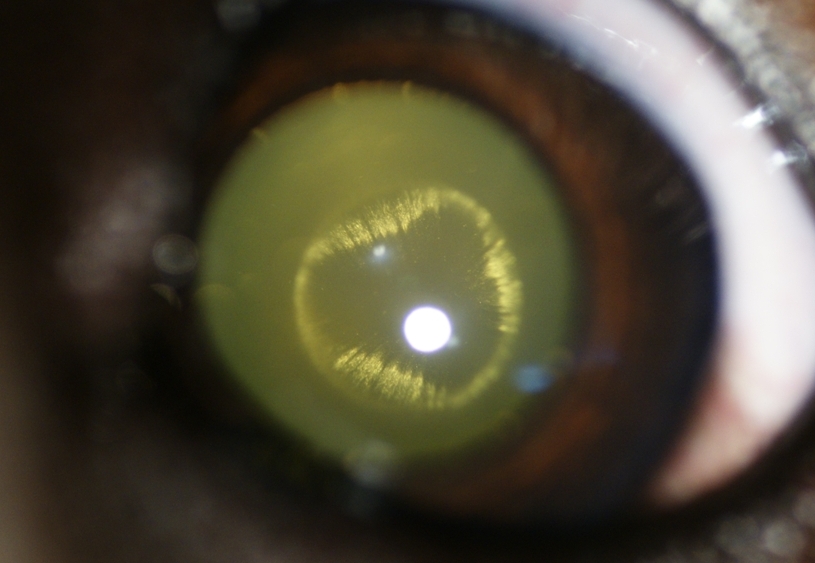

Cataracte périnucléaire postérieure chez un chiot

- 64532 (273.9 Kio) Consulté 2728 fois